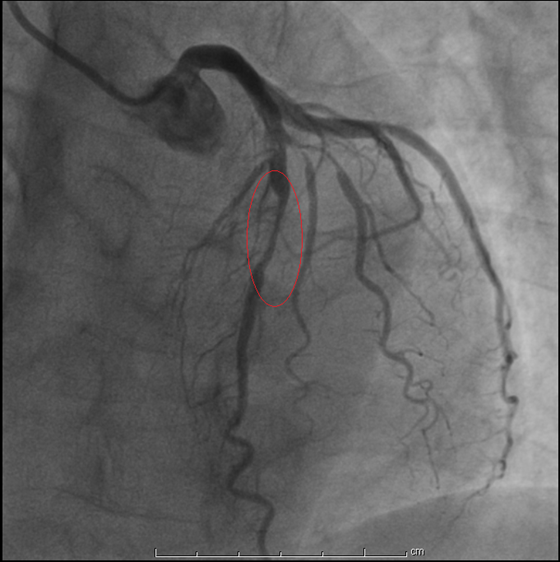

今年2月底,刘阿姨来到湘雅常德医院心内科,范爱德副主任医师仔细询问病史后,结合患者各种检查认为还是要考虑冠心病 心绞痛可能,建议刘阿姨住院,进一步完善冠脉造影明确冠心病。2月27日,据刘阿姨的冠脉造影显示,她的三条动脉都有不同程度的狭窄,其中一条动脉(左前降支)重度狭窄并钙化。心内科为刘阿姨做了冠脉介入治疗手术,于前降支近段及中段狭窄处植共植入2枚支架后,狭窄的血管顺利开通,心肌得到供血。历时近一年的求医之路,今天终于看到曙光,刘阿姨放心了……

支架植入术前